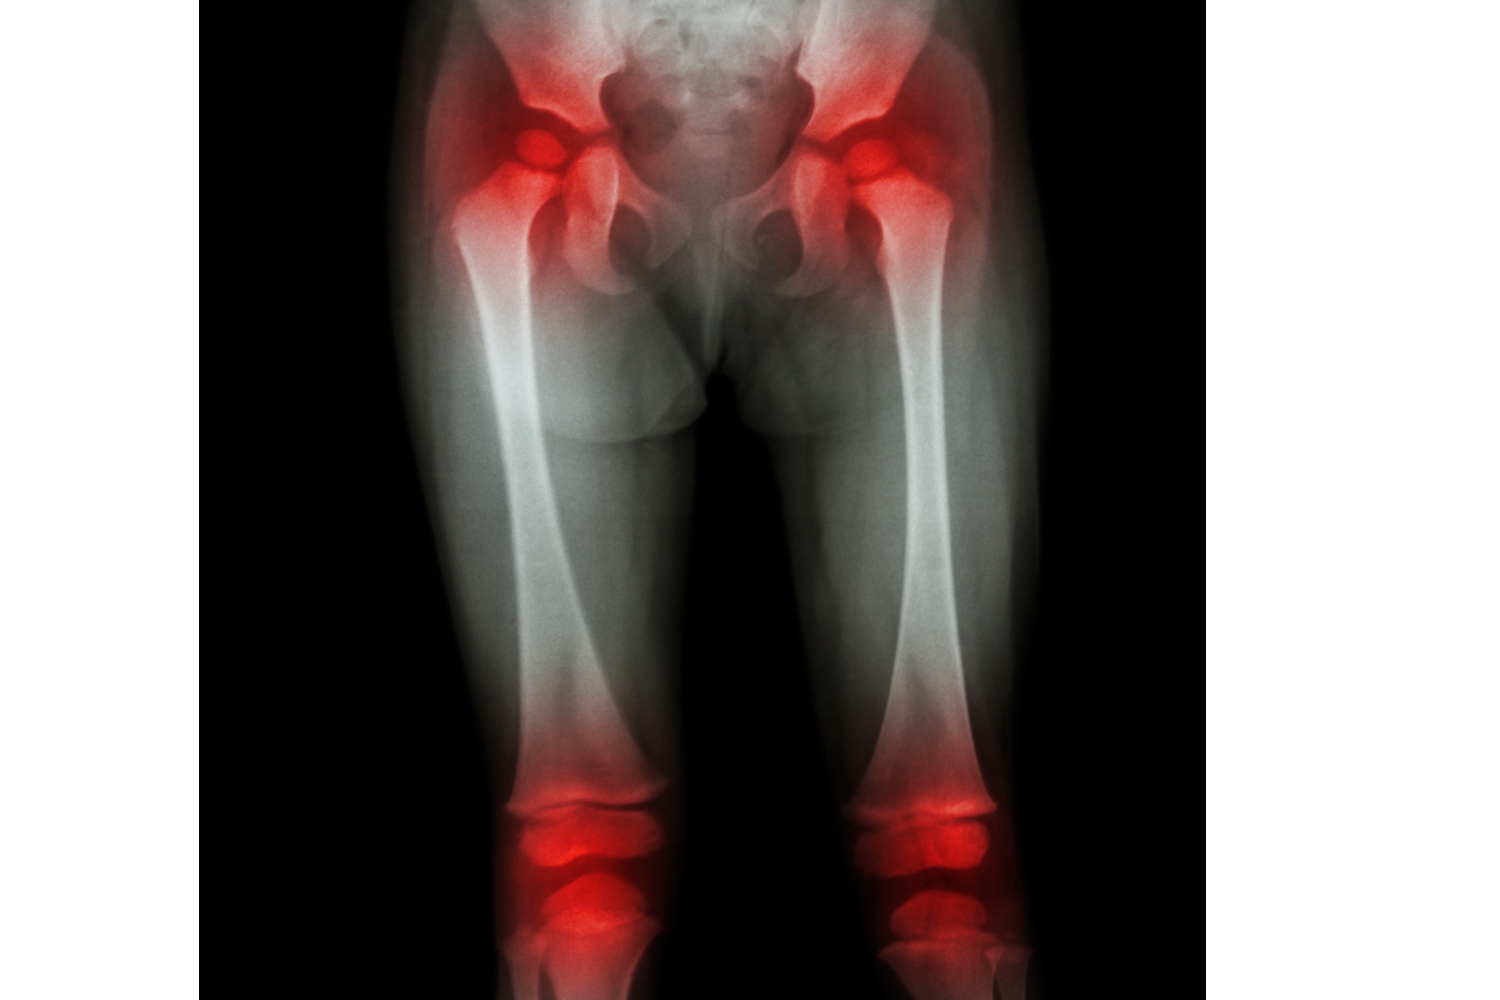

This is the most common type of JIA, which affects fewer than five joints in the body. The impact is seen within the first 6 months of infection. It will mostly affect the knees, wrists, and ankles. In some cases, it can also affect the eye, particularly the iris – known as iritis or iridocyclitis. It is more prevalent among girls than among boys. Most children will outgrow this type of JIA when they reach adulthood.

Also known as pJIA, affects 5 or more joints within the first 6 months of the infection itself. It is more common among girls than boys. A viral infection can also be its trigger. In some cases, it can present itself as acute episodes, while in some cases it can be a chronic condition that can last for months. When it affects a joint, it affects the same joint on both sides of the body, both the knees, both the elbows, both the ankles, both the wrists, etc. It can also affect the joints in the neck and jaw.

5. Enthesitis-Related Arthritis

This form of JIA predominantly affects the lower part of the body. It can affect the spine, hips, enthuses, and can eventually even affect the sacroiliac joints and the spine. It can result in juvenile ankylosing spondylitis. This condition is more common among boys above the age of eight than girls. Children with a male relative diagnosed with ankylosing spondylitis are at a higher risk of contracting this form of JIA. Some studies also show that children of Asian ethnicities are at a higher risk.

- MRI scans

- Ultrasound

- X-rays